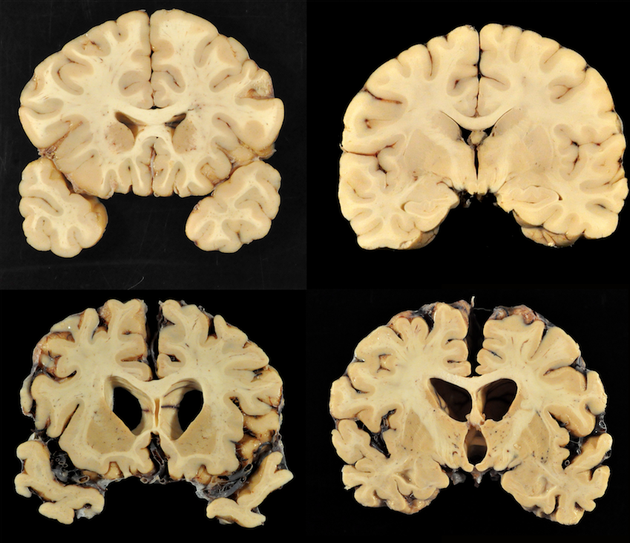

Brain Injury Cte Found In 87 Of Football Players Brains Time

Bu Researchers Find Cte In 99 Of Former Nfl Players Studied The

99 Percent Of Studied Nfl Brains Diagnosed With Cte Researchers